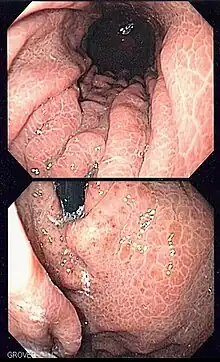

Vue intérieur de l’estomac grâce à une gastroscopie.

- Endoscopie de l’estomac.

La gastroscopie, ou plus précisément l'œso-gastro-duodé- noscopie, est devenue, depuis son introduction il y a environ 20 ans, l'examen de référence pour l'exploration du tractus digestif haut, jusqu'à la deuxième portion du duodénum.

— (Jacques Frexinos & Louis Buscail, Hépato-gastro-entérologie proctologie, pour le praticien, Éditions Masson, 2004, p. 59)La gastroscopie est une exploration visuelle, qui sert à mettre en évidence des lésions de l'œsophage, de l'estomac et du duodénum.